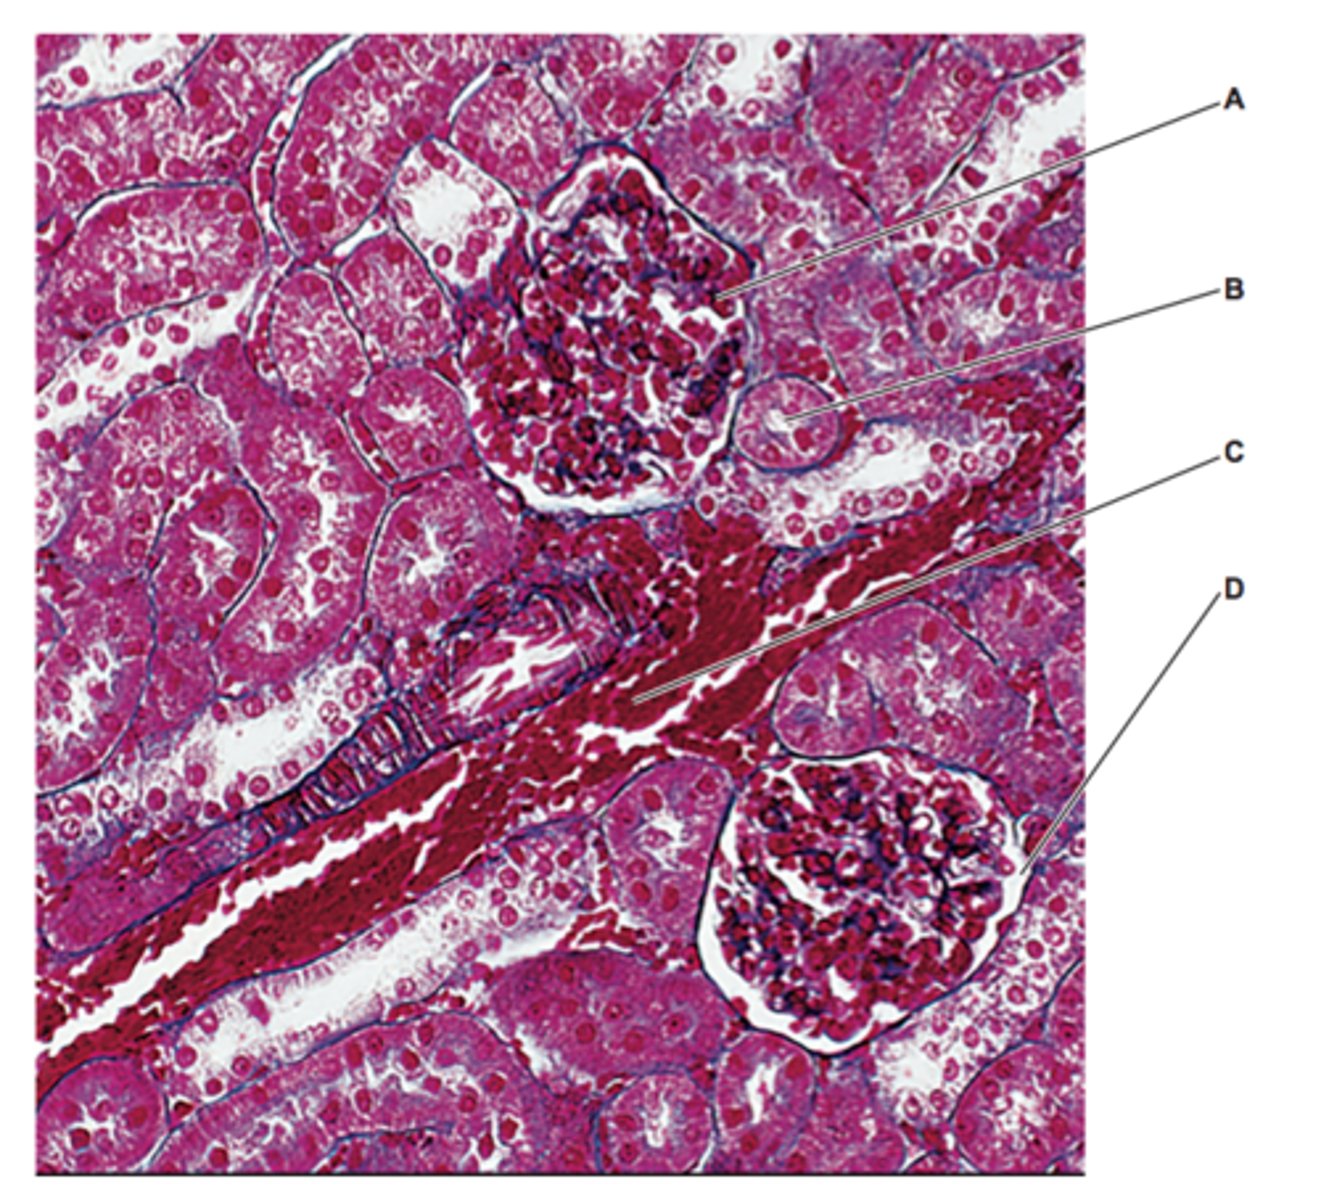

name A-D

A - glomeruli

B - PCT

C - renal artery

D - bowman's capsule

(these are my guesses as the mark scheme don't have the actual answers)

A - glomerulus

B - bowman's capsule

name A & B

A - bowmans capsule

B - glomeruli

how do you distinguish between the PCT and DCT under a microscope?

PCT will have microvilli whereas DCT will not